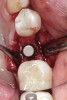

Fig 11. An implant was placed in regenerated bone.

Figure 11